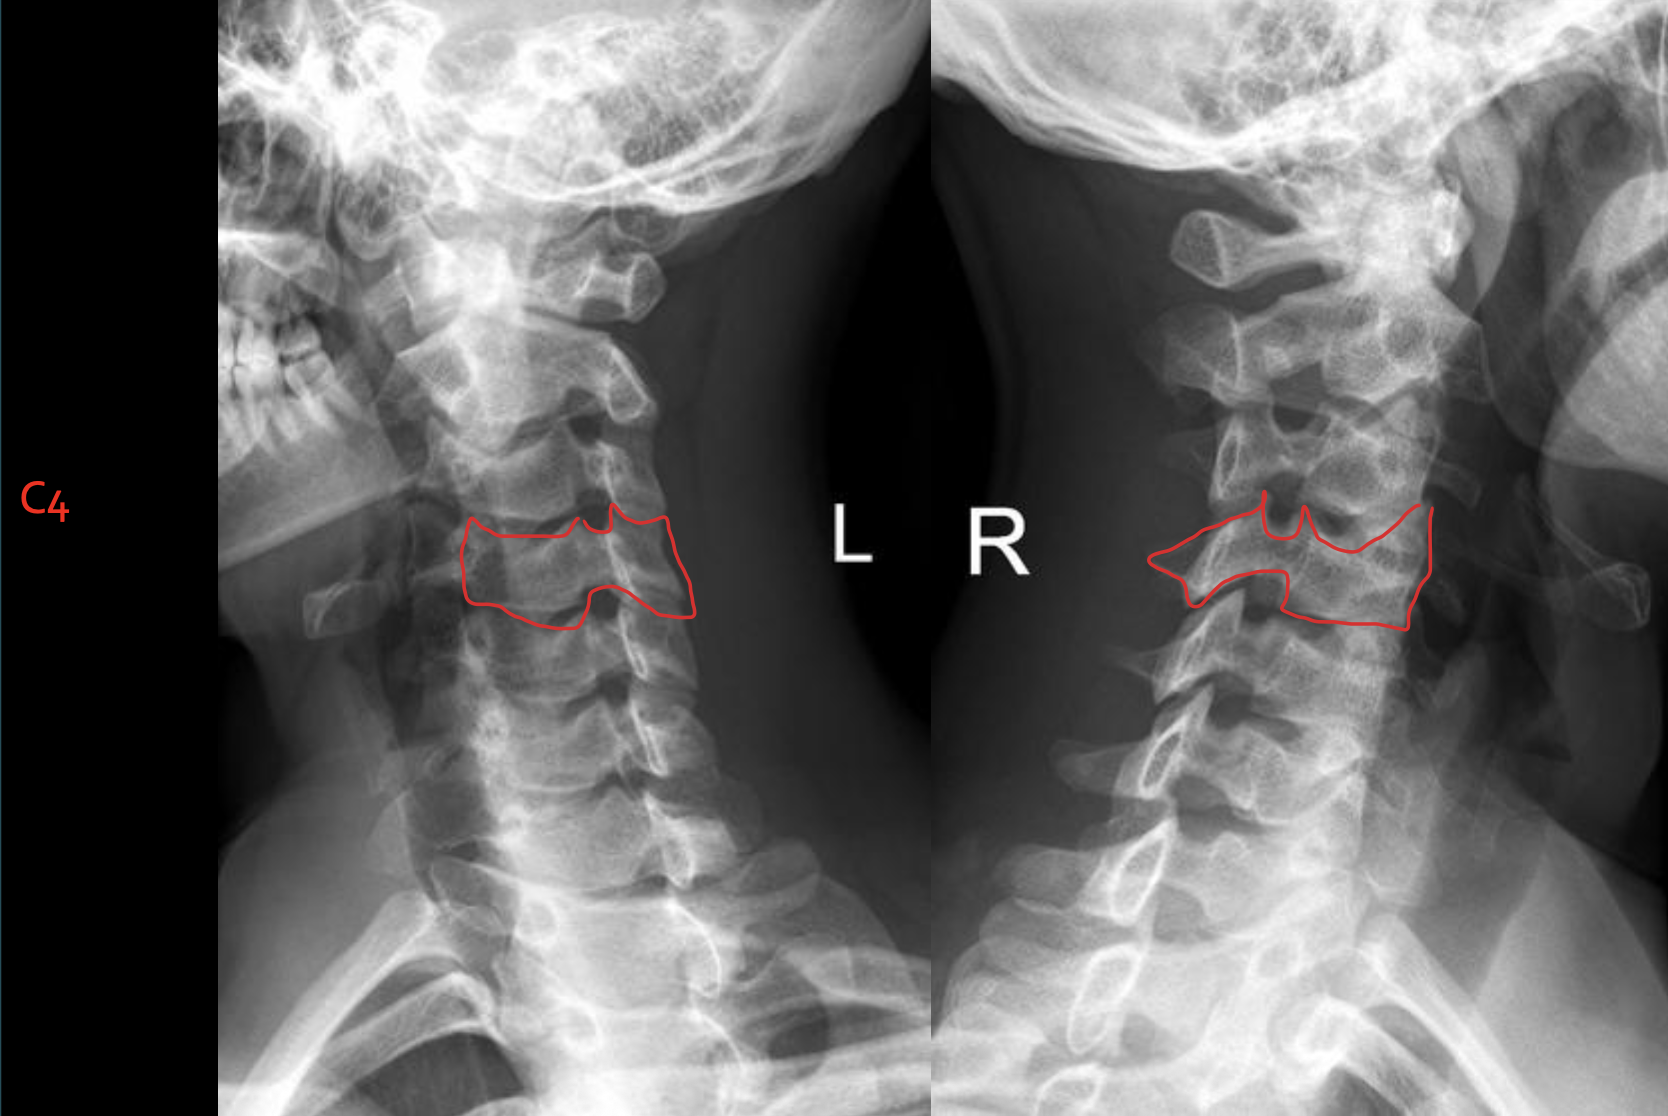

C4